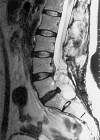

Intraoperative monitoring (IOM) of bladder function in spinal cord surgery is a challenging task due to vegetative influences, multilevel innervation and numerous supraspinal modulating factors. Despite routine use of urodynamics in neurosurgery for implantation of bladder stimulators or denervation of nerve fibres in spastic reflex bladders, application of IOM in patients with spinal cord tumours or tethered-cord syndrome is not widespread. Combining urodynamics with sphincter electromyography (EMG) in IOM enables identification of bladder efferents responsible for contraction and continence. We monitored four patients with ependymoma of the Cauda equina, one patient with tethered-cord syndrome and two patients with cervical intramedullary tumours. In all patients undergoing operations of the Cauda equina, identification of bladder efferents responsible for detrusor contraction was possible. There was good correlation between preoperative bladder dysfunction, preoperative urodynamics and intraoperative pressure increase by bladder contraction or latency between stimulation and contraction. This method proved unsuitable for intramedullary tumours where no contraction of the bladder could be observed while stimulating the spinal cord. Intraoperative monitoring of urodynamics is an effective tool for identifying bladder efferents in the Cauda equina. Intraoperative conclusions on bladder dysfunction through registration of pressure increase and latency are possible.